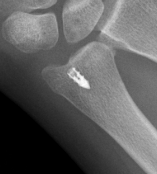

Ulna styloid process fracture and acute DRUJ instability

Ulna styloid fracture with TFCC injury

- ulna styloid ORIF

AO surgery ulna styloid fracture screw fixation

AO surgery ulna styloid TBW fixation